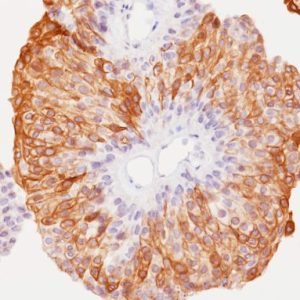

Bladder